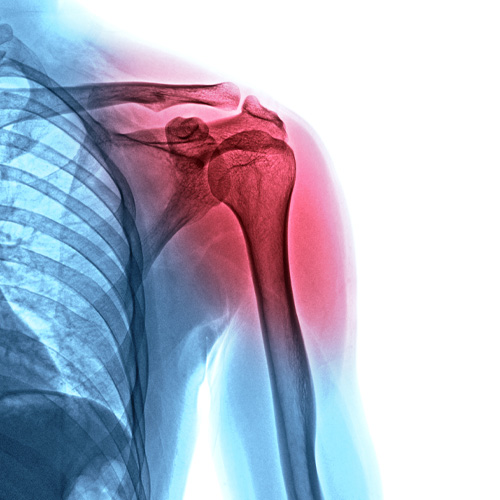

Why Throwing Puts the Shoulder and Elbow at Risk

It may surprise you, but throwing is actually one of the most demanding motions in sports. It’s a complicated movement that requires the arm to move at high speed while repeatedly absorbing large forces. If any part of the system breaks down, stress shifts to places that aren’t built to handle it.

Some of the throwing-related injuries we see include:

- Rotator cuff strain, where the small stabilizing muscles in the shoulder become overloaded or fatigued

- Labral irritation, where the cartilage ring that helps stabilize the shoulder becomes stressed

Shoulder Stability: The Base of a Healthy Throw

Your shoulder blade controls how your arm moves and how force is transferred. When it lacks control, your rotator cuff works harder than it should and your elbow absorbs more force. As a result, the entire upper extremity can become fatigued more easily, setting you up for an injury.